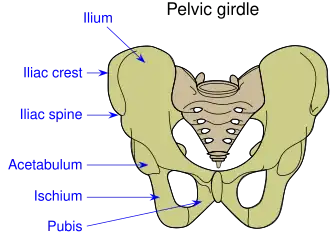

Pelvic girdle | |

The acetabulum (/ˌæsɪˈtæbjələm/;[1] pl.: acetabula), also called the cotyloid cavity, is a concave surface of the pelvis. The head of the femur meets with the pelvis at the acetabulum, forming the hip joint.[2][3]

Structure

There are three bones of the os coxae (hip bone) that come together to form the acetabulum. Contributing a little more than two-fifths of the structure is the ischium, which provides lower and side boundaries to the acetabulum. The ilium forms the upper boundary, providing a little less than two-fifths of the structure of the acetabulum. The rest is formed by the pubis, near the midline.